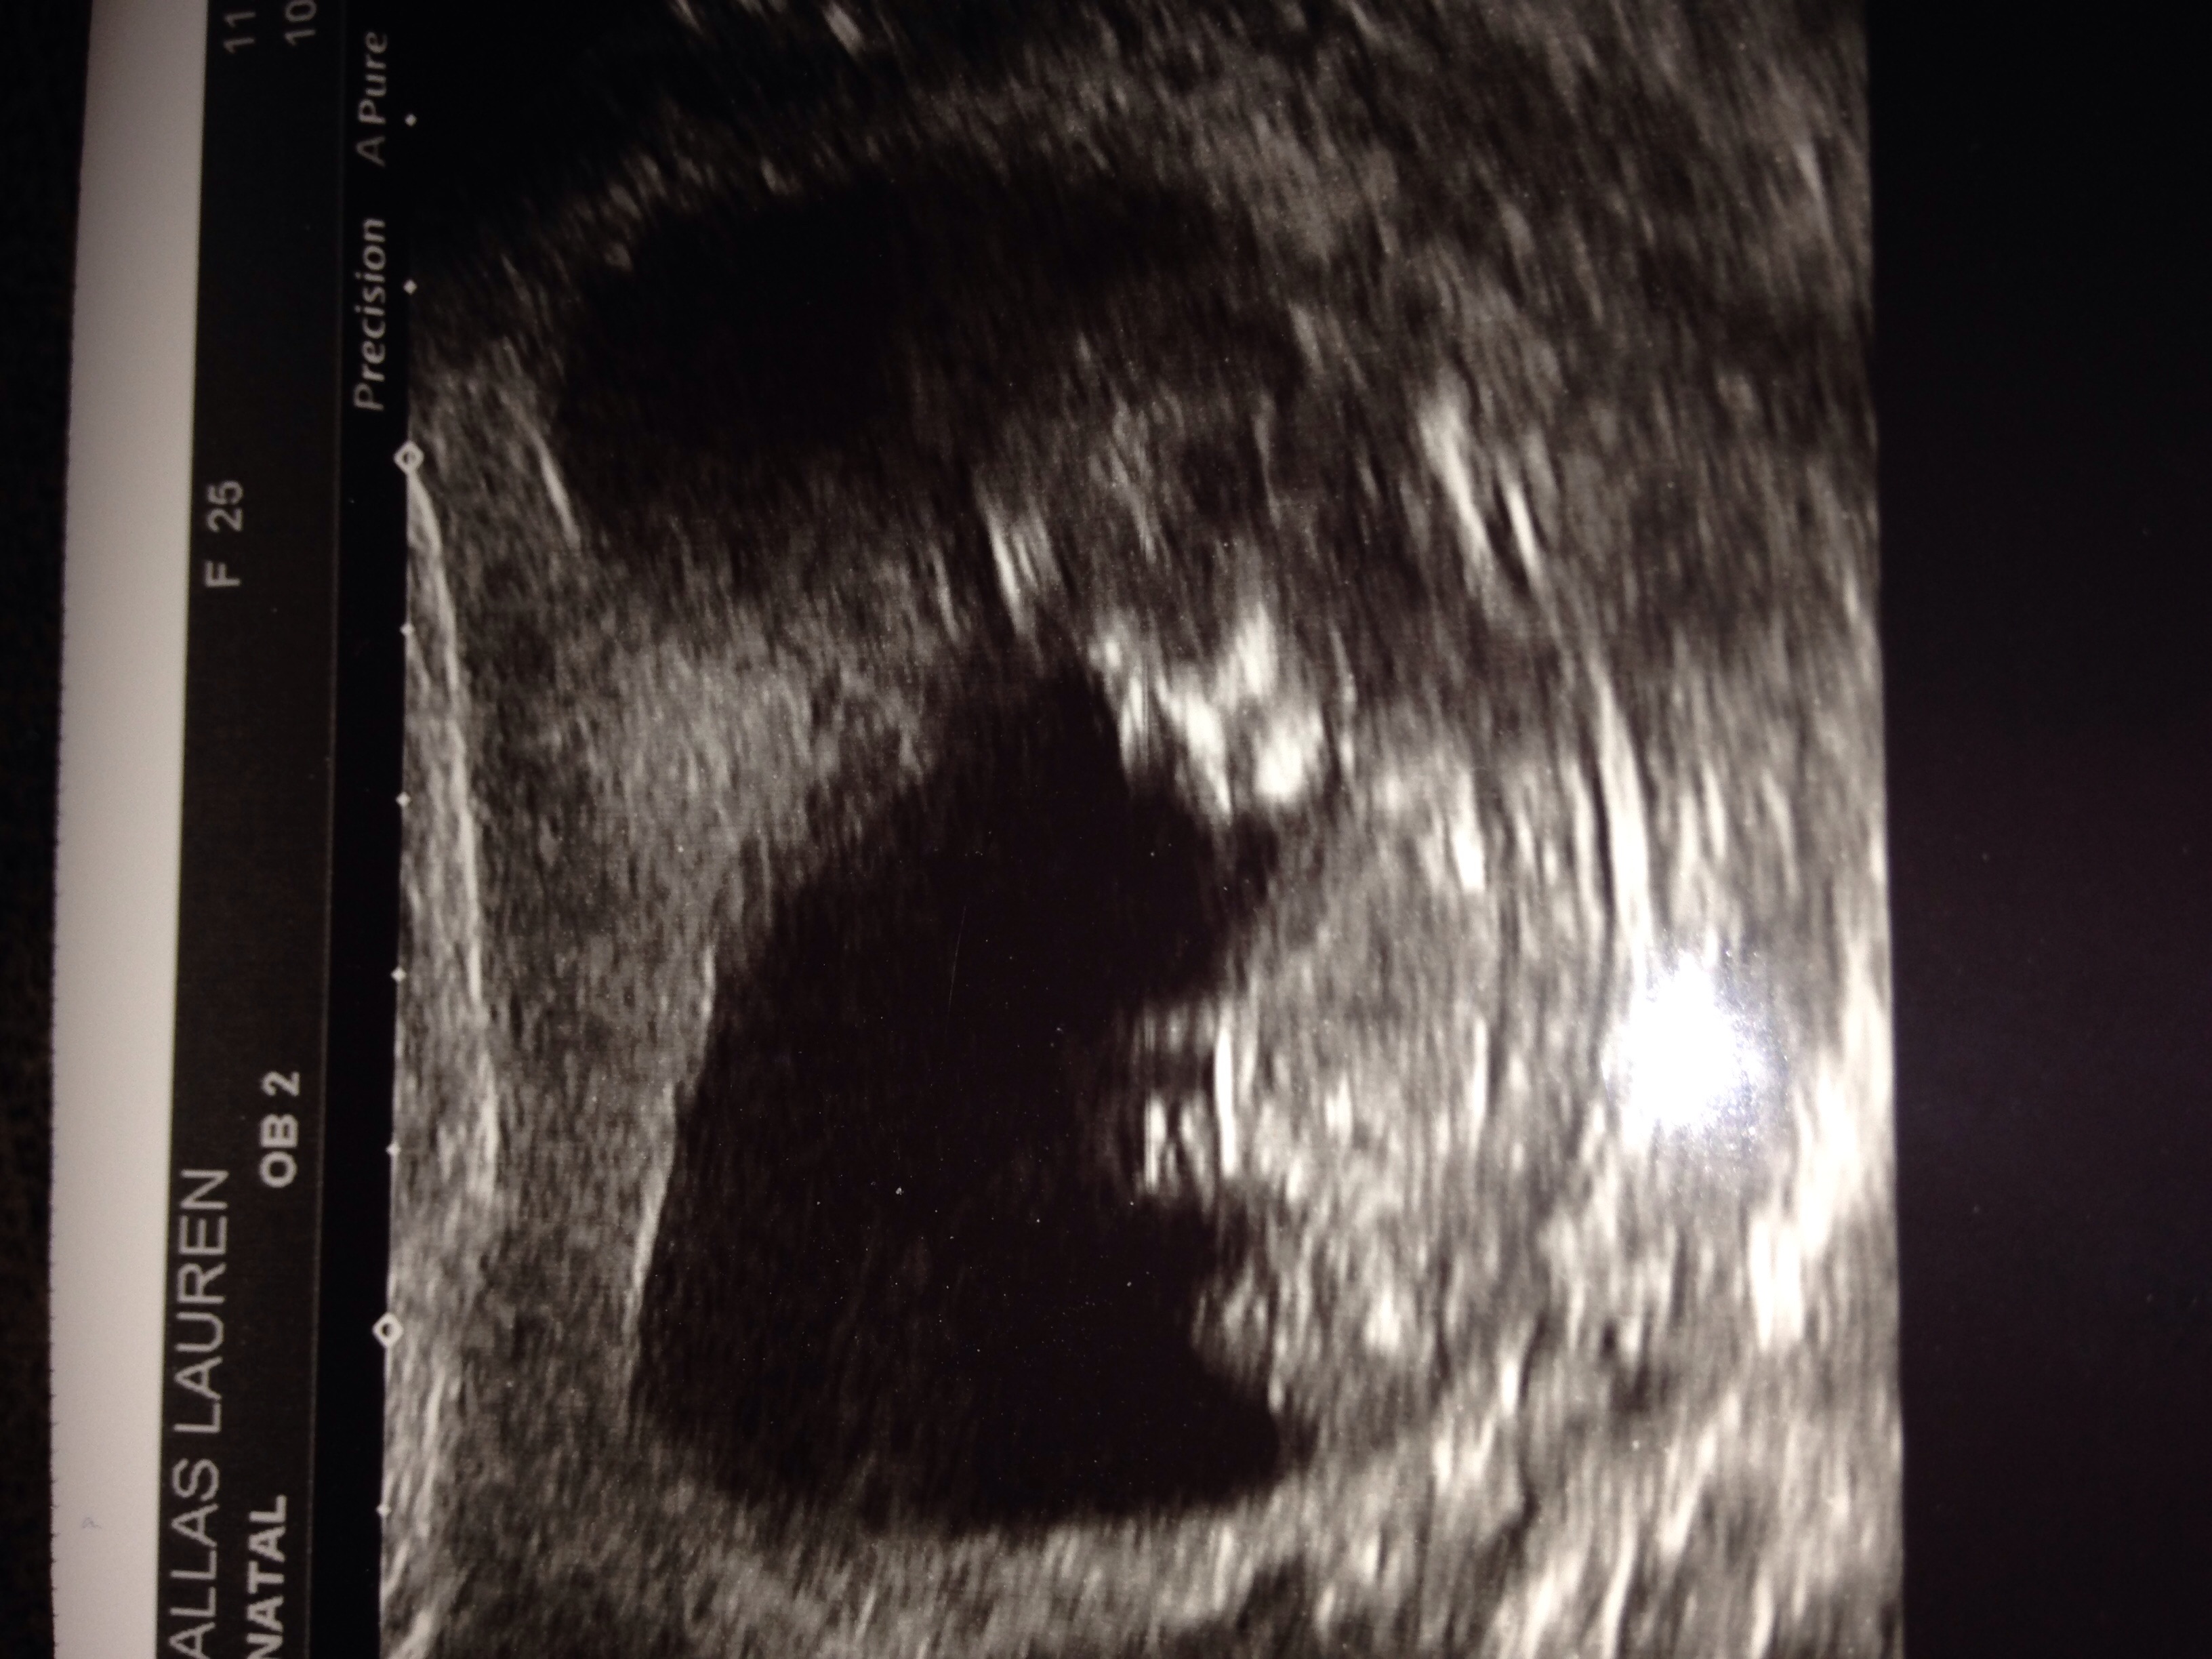

This is my 3rd child I'm eager to find out people's opinions be it nub / skull theory ? Pic from 12week +2 ... Also have a pic from 6week +2 which may be good for ramzi predictions? I can't even find nub so any help greatly appreciated xxxAttachment 27269